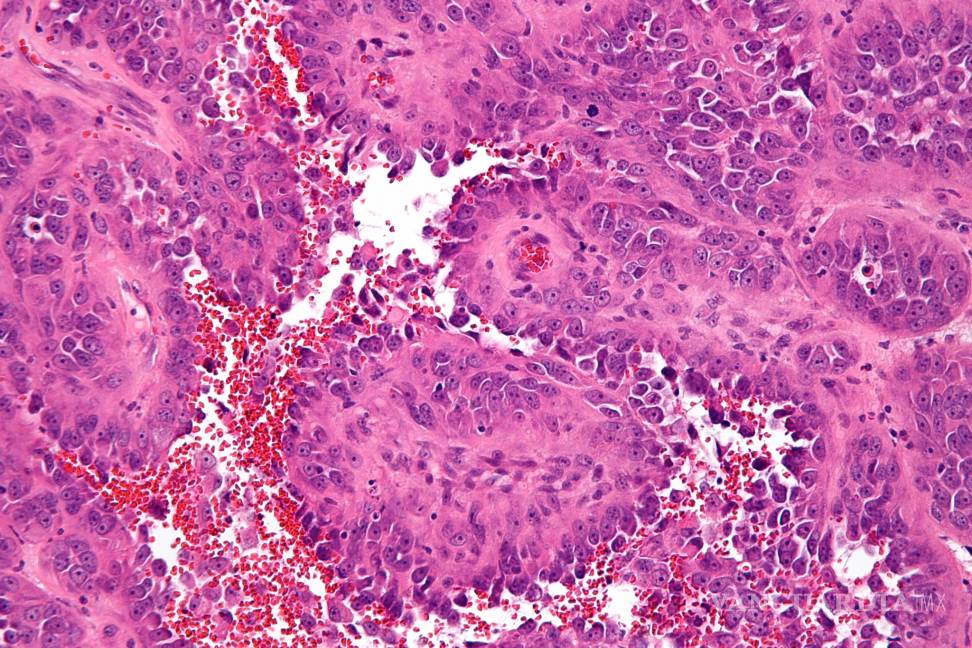

El estudio que es el resultado del Proyecto Angiosarcoma identificó nuevas causas del angiosarcoma, un cáncer poco frecuente de las paredes de los vasos sanguíneos, que podría aportar nuevas terapias.

Una investigación con pacientes del Broad Institute of MIT and Harvard (Estados Unidos) identificó nuevas causas del angiosarcoma, un cáncer poco frecuente de las paredes de los vasos sanguíneos, que podría aportar nuevas terapias, reveló hoy un artículo publicado en Nature Medicine.

Este tipo de cáncer, cuya agresividad es muy alta, puede ocurrir en cualquier parte del cuerpo, pero con mayor frecuencia se produce en la piel, el pecho, el hígado y el bazo.